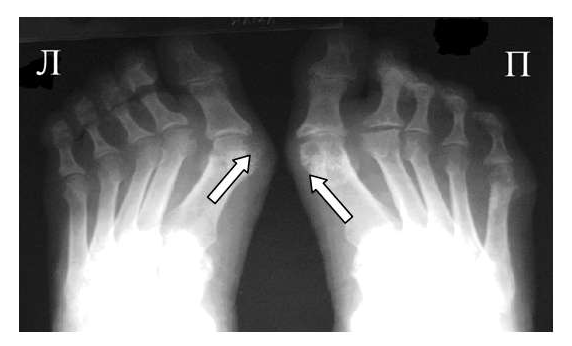

Также хотелось обратить внимание на неправильно выбираемую зону обследования. Например, зачастую при наличии односторонних клинических изменений в одном пястно-фаланговом или плюсне-фаланговом суставе врачи ограничиваются рентгенографией исключительно этой области. Однако, именно характер патологических изменений в обеих кистях, их локализация и распространённость, анализ того какие группы суставов изменяются в самом начале заболевания должны обязательно учитываться при оценке рентгенограмм для того, чтобы правильно интерпретировать полученные данные и провести дифференциальный диагноз между различными ревматическими заболеваниями. Поэтому в ревматологической практике для уточнения диагноза необходимо проводить по показаниям либо прямую сравнительную рентгенограмму кистей с захватом лучезапястных суставов либо прямую сравнительную рентгенограмму стоп.

Исходя из нашего опыта, результаты рентгенографии нередко могут зависеть от техники и правильного позиционирования объекта съемки. В настоящее время требованием всех протоколов исследований является соблюдение максимально унифицированных условий проведения рентгенограмм кистей и стоп. Так для общей оценки поражения суставов необходимо снимать обе кисти или стопы на одной пленке, обязателен захват лучезапястного сустава. Требования к расположению пациента при рентгенографии кистей и стоп изложены в соответствующих руководствах по рентгенологии. Врачу общей практики при направлении к рентгенологу обязательно необходимо указывать, что больной направляется на сравнительную рентгенограмму кистей в прямой проекции с захватом лучезапястных суставов или на прямую сравнительную рентгенограмму стоп.